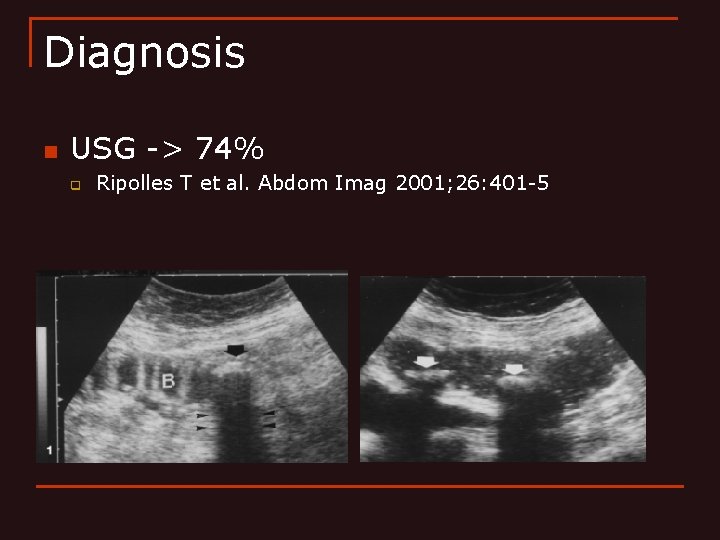

Diagnosis n USG -> 74% q Ripolles T et al. Abdom Imag 2001; 26: 401 -5